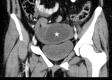

Case presentation: A 16-year-old female presented to the emergency department with acute onset of right lower quadrant abdominal pain for several hours. The patient was afebrile and physical examination was notable for isolated tenderness in the right lower quadrant. Ultrasound and computed tomography demonstrated an adnexal cystic structure. Pelvic magnetic resonance imaging was ordered to better characterize the pathology.